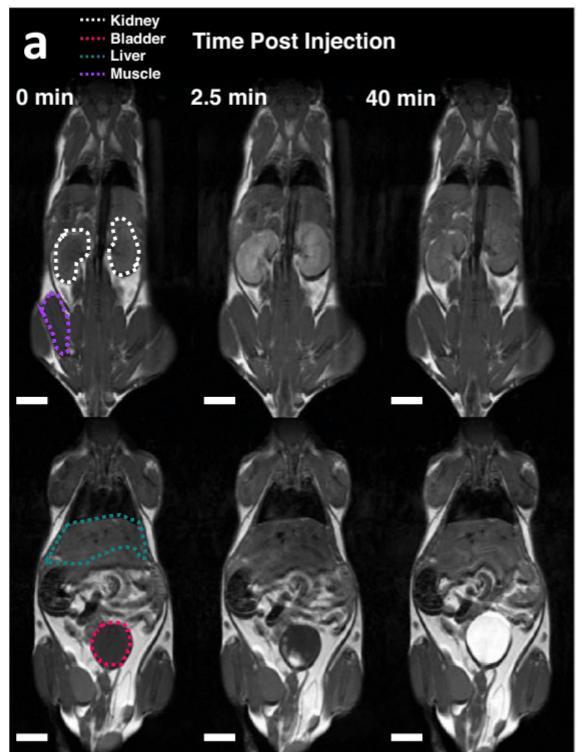

MRI Studies: oc-glucoverdazyl

In 2024, Calvert et al demonstrated that oc-glucoverdazyl was a viable MRI contrast agent with appropriate biological properties that included stability in mouse serum, negligible binding to human serum albumin, was cytocompatible with human renal proximal tubule cells, and was not absorbed by glucose-starved HepG2 cells.6 Using DCE-MRI with ocglucoverdazyl, they were able to measure unilateral ureteral obstruction in a series mouse models, though oc-glucoverdazyl had a short half-life with MRI images being collected 2.5 min post injection.

Preliminary in vivo MRI Studies

Contrast enhancement was observed in the left kidney (with longer retention than the ocglucoverdazyl) and the bladder We also have data that indicates that our compound is absorbed by the pancreas While we observed no noticeable ill-effects on the mouse, we will be examining the vital organs using the Fred Hutch pathology facilities